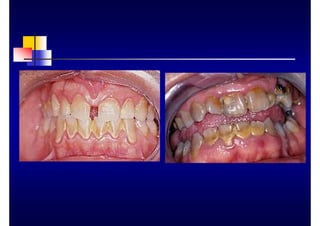

CLÍNICA DE LA PERIODONTITIS

ASOCIADA AL TABACO

• Encía fibrótica, con engrosamiento de los

márgenes

• Mínimo enrojecimiento gingival en relación con

la gravedad de la enfermedad

• Mayor gravedad y progresión en relación con

los no fumadores de la misma edad

• Recesión gingival en segmentos anteriores

• No existe relación entre el estado periodontal y

el nivel de placa y cálculo

• Inicio de la enfermedad relativamente temprano,

entre los 20 y los 30 años

• Progresión rápida de la enfermedad

• Reaparición de bolsas después de un año del

tratamiento

• Resistencia al tratamiento convencional

Haber J Current in Periodontology 1994: 12-8